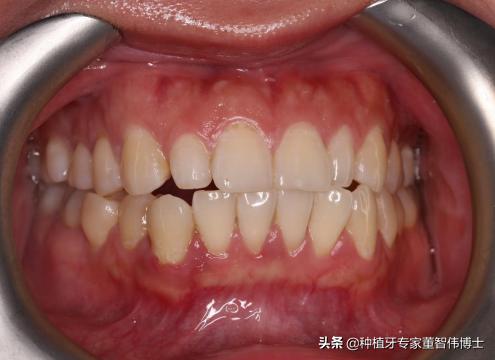

术前